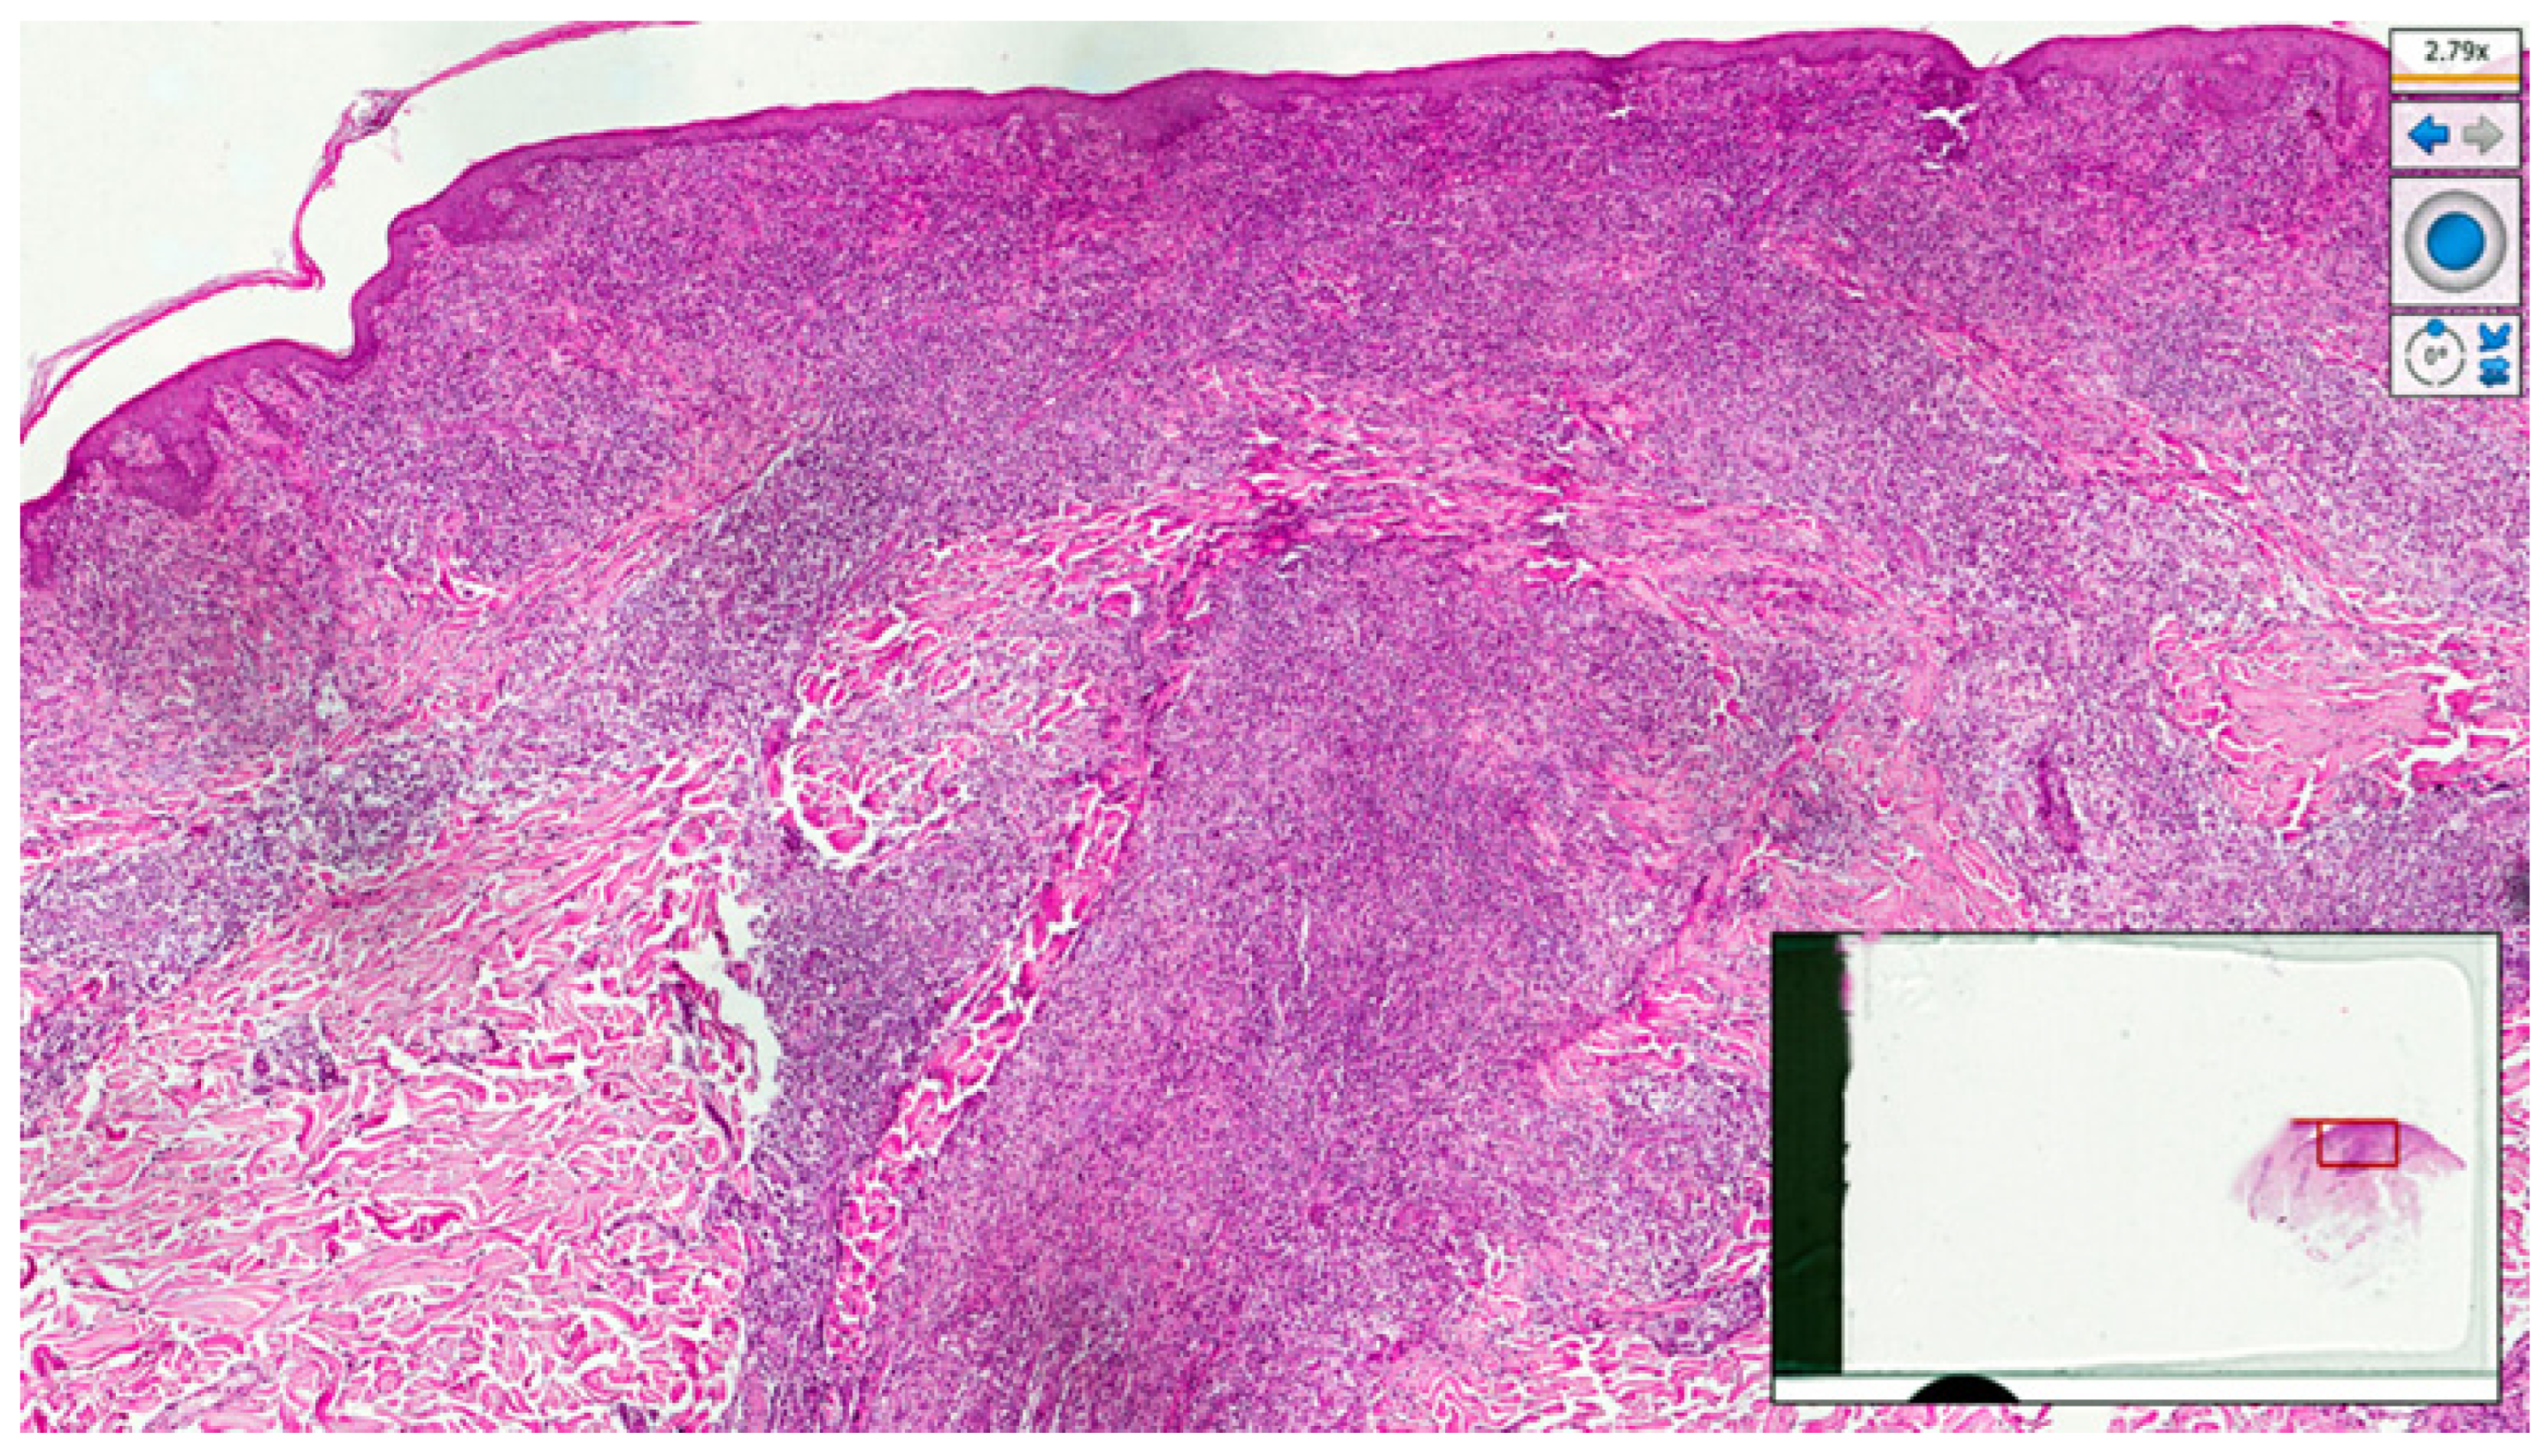

2. Case Presentation